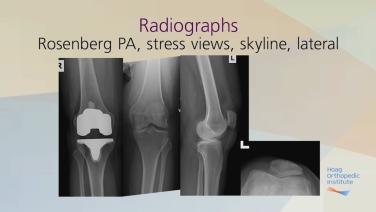

Current Techniques & Fixation in Total Knee Arthroplasty: Case Examples

Cementing Practices in Total Knee Arthroplasty: Case Examples